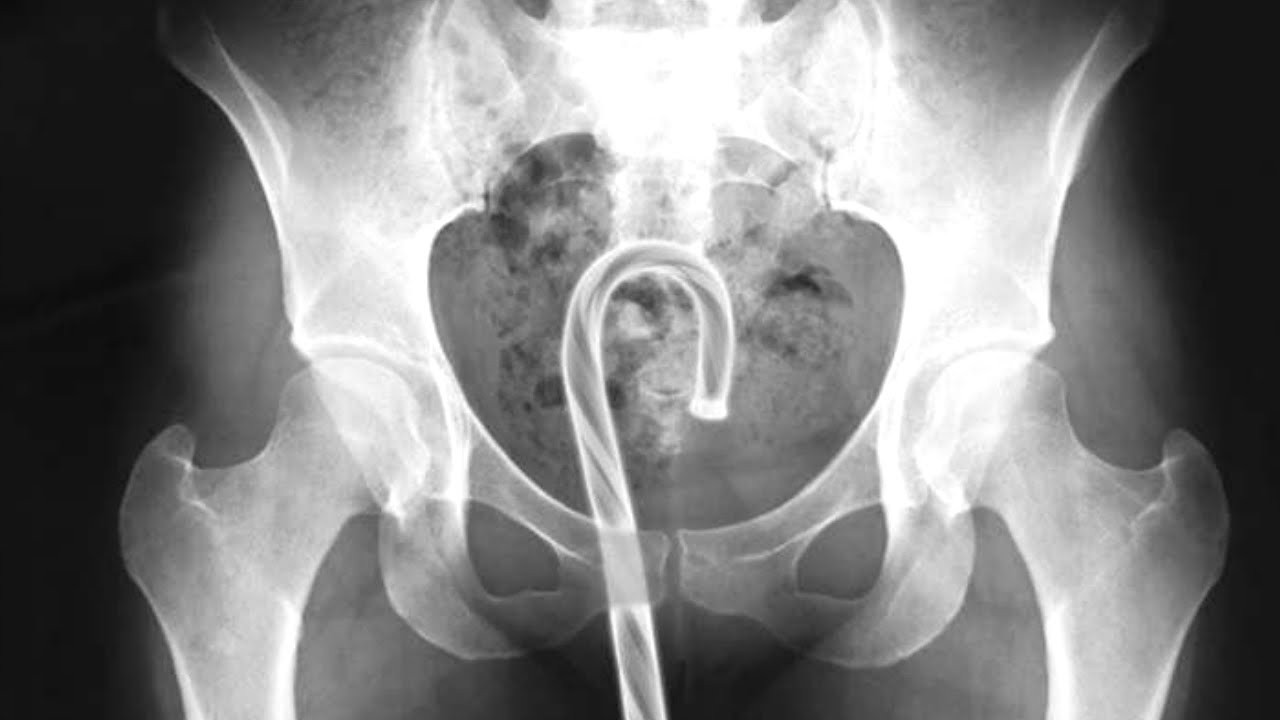

Happy Holidays to one and all. It’s time to gather ’round the fire with your loved ones for our nation’s oldest and finest tradition: reading about people that jammed things in their holes and couldn’t get them out without medical intervention. All reports are taken from the U.S. Consumer Product Safety Commission’s database of emergency room visits, […]

list is broken down by orifice. here’s the most important one (Rectum? Damn near killed ’em!):